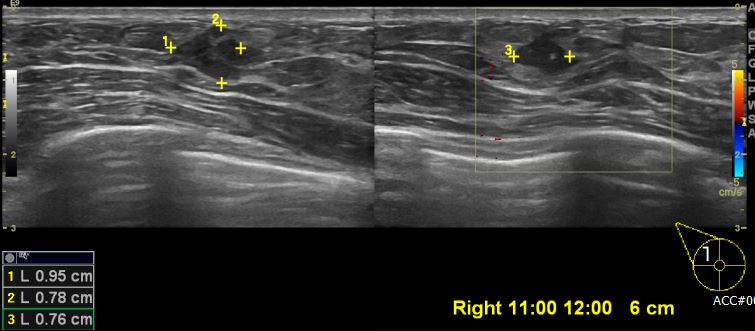

상기환자 건강검진상 이상 소견으로 내원하신 40대 여성분으로 우측 의심스러운 혹 조직검사 시행하여 우측 침윤성 유관암 진단 되었습니다.